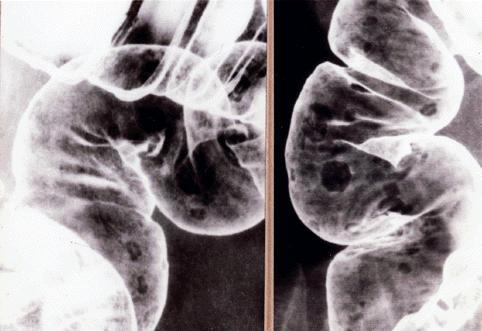

過形成ポリポーシスのX線像  S状結腸(左)と上行結腸(右)の注腸二重造影写真です。1mmから7mm大の微小~小隆起が多発しています。形は類円形が多いのですが、その辺縁はいずれも不整で角張っています。また隆起の中央部には、そのほとんどが臼歯の表面をみるような不整形の凹みを伴っています。

疾患(病理主体)の分類腫瘍様病変/過形成ポリポーシス

病変の最大径(ミリ)1〜9

多発腫瘍(同一臓器)有(同時性)